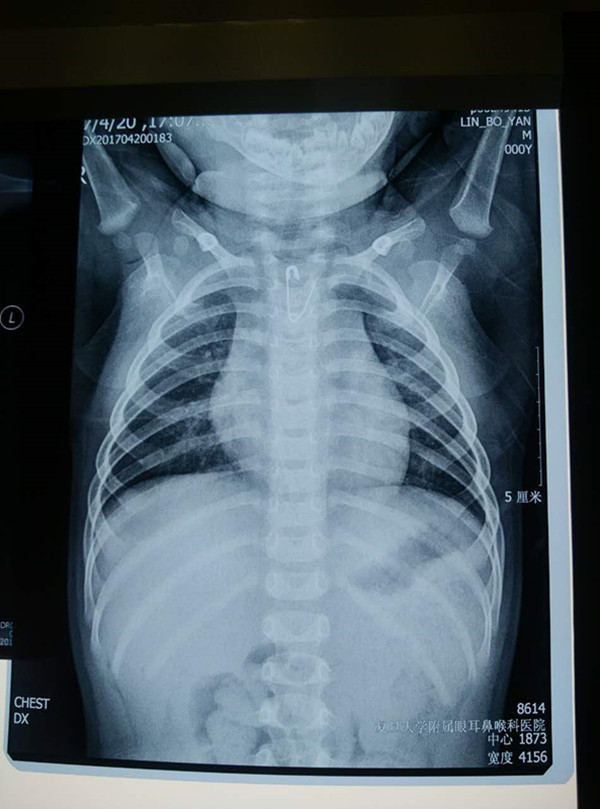

據(jù)介紹,九月齡的江蘇小男嬰床頭有著一塊帶有別針的小手帕,20日上午母親發(fā)現(xiàn)手帕上的別針不見(jiàn)了,雖然男嬰未出現(xiàn)明顯不適,但父母懷疑他誤吞了別針,隨即送至江西省兒童醫(yī)院就診,胸片結(jié)果顯示,一枚呈V字形的開(kāi)口別針卡在男嬰的食道里,針頭向上,接連輾轉(zhuǎn)兩家醫(yī)院后,男嬰于14小時(shí)后被兒科醫(yī)院收治。